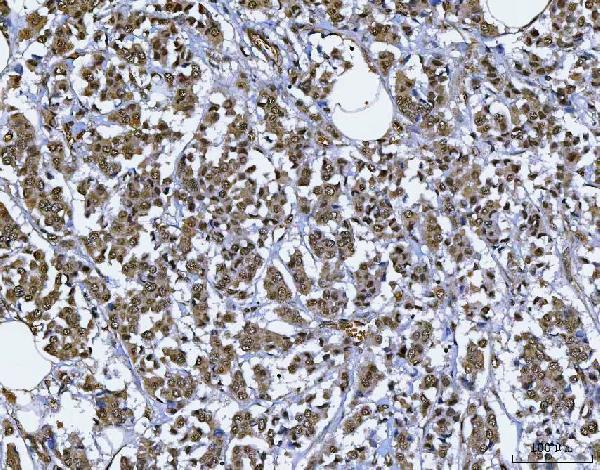

Facts about SWI/SNF-related matrix-associated actin-dependent regulator of chromatin subfamily E member 1.

| Gene Name: | SMARCE1 |